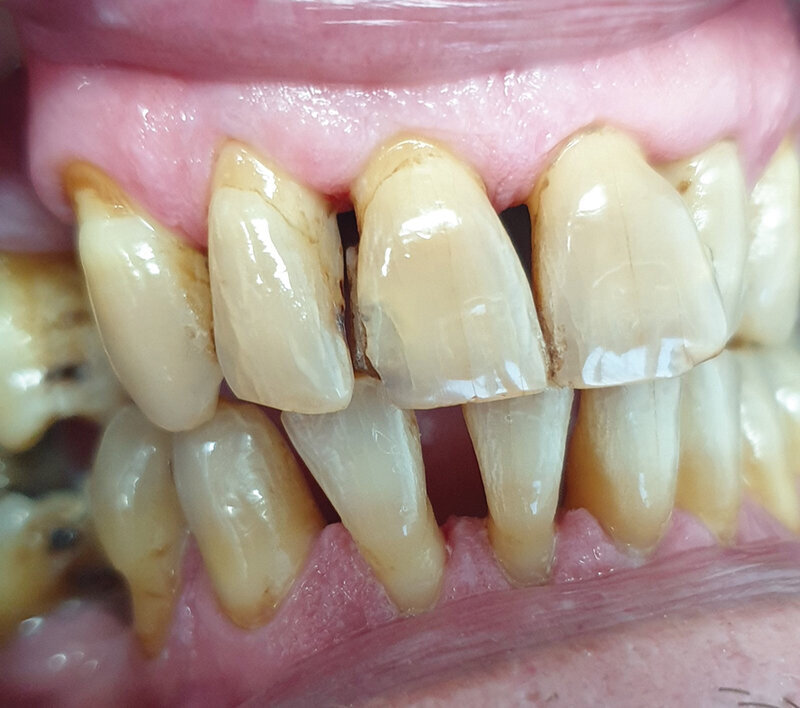

Pacijent B pušač pri prijemu. Estetski neprihvatljive pušačke pigmentacije na svim površinama zuba, naročito onim u estetskoj zoni, direktno izloženim glavnoj struji duvanskog dima. Zubni kamenac i meke naslage ukazuju na nizak nivo oralne higijene. Uočava se i prebojenost kompozitnih aproksimalnih plombi gornjih prednjih zuba. Slabije izražene melanogene pigmentacije desni. Jezik pacijenta takođe je obložen (Sl. 2.0).

Sl. 2.0: Pacijent B, pušač pri prijemu